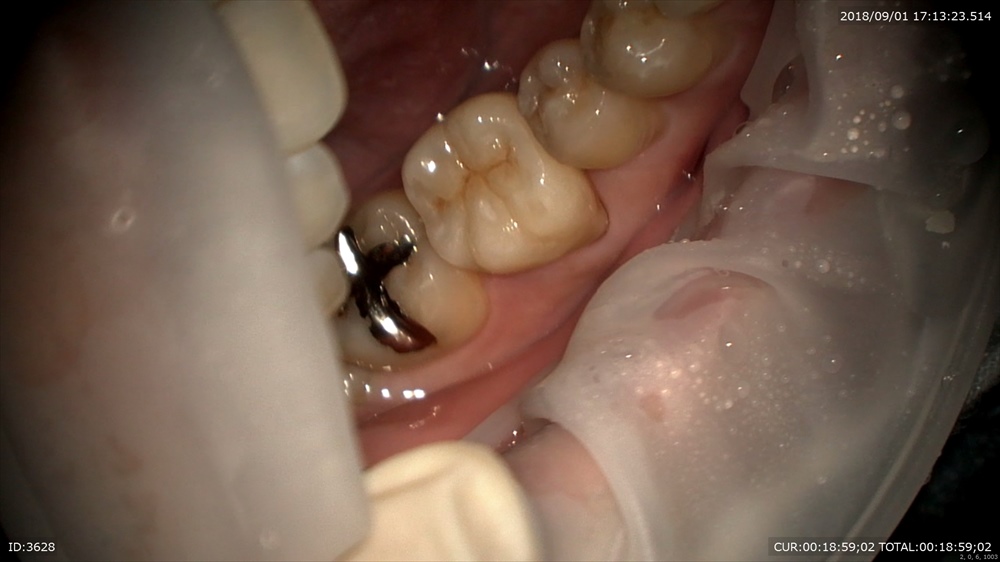

歯周病治療後型取りをして

本日セット 技工士間中先生

少しの段差もありません、

このように重症の虫歯でも抜歯せずに治療ができます。ただし、

「準備、手間ヒマ、毎日の修行、人がやらない事を一生懸命やる」

これが大切だと思います。

これは寿司屋さんに共通すると思いました。